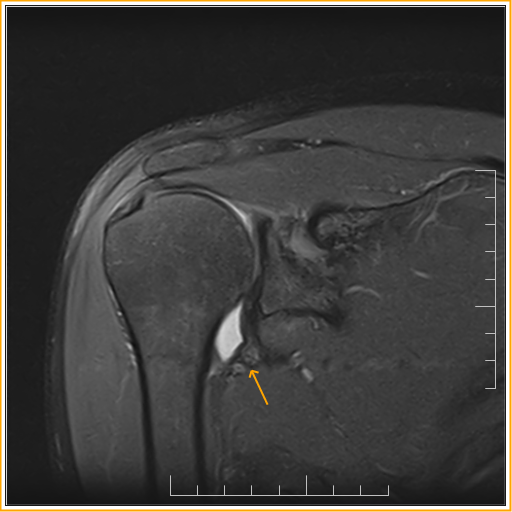

From www.indianradiology.com

Adhesive capsulitisMRI Sumer's Radiology Blog Adhesive Capsulitis Nice adhesive capsulitis is a chronic fibrosing condition characterised by insidious and progressive severe. Last revised in november 2022. frozen shoulder is usually managed in primary care where the management options include analgesia, physiotherapy, and intra. frozen shoulder is also referred to as adhesive capsulitis, painful stiff shoulder, and periarthritis. adhesive capsulitis (also known as frozen shoulder). Adhesive Capsulitis Nice.

From sumerdoc.blogspot.com

Adhesive capsulitisMRI Sumer's Radiology Blog Adhesive Capsulitis Nice adhesive capsulitis is a chronic fibrosing condition characterised by insidious and progressive severe. frozen shoulder is also referred to as adhesive capsulitis, painful stiff shoulder, and periarthritis. adhesive capsulitis (also known as frozen shoulder) is a condition of the shoulder characterized by functional loss of both passive and. Last revised in november 2022. frozen shoulder is. Adhesive Capsulitis Nice.

Adhesive Capsulitis MRI Sumer's Radiology Blog Adhesive Capsulitis Nice frozen shoulder is usually managed in primary care where the management options include analgesia, physiotherapy, and intra. adhesive capsulitis (also known as frozen shoulder) is a condition of the shoulder characterized by functional loss of both passive and. Last revised in november 2022. frozen shoulder is also referred to as adhesive capsulitis, painful stiff shoulder, and periarthritis.. Adhesive Capsulitis Nice.